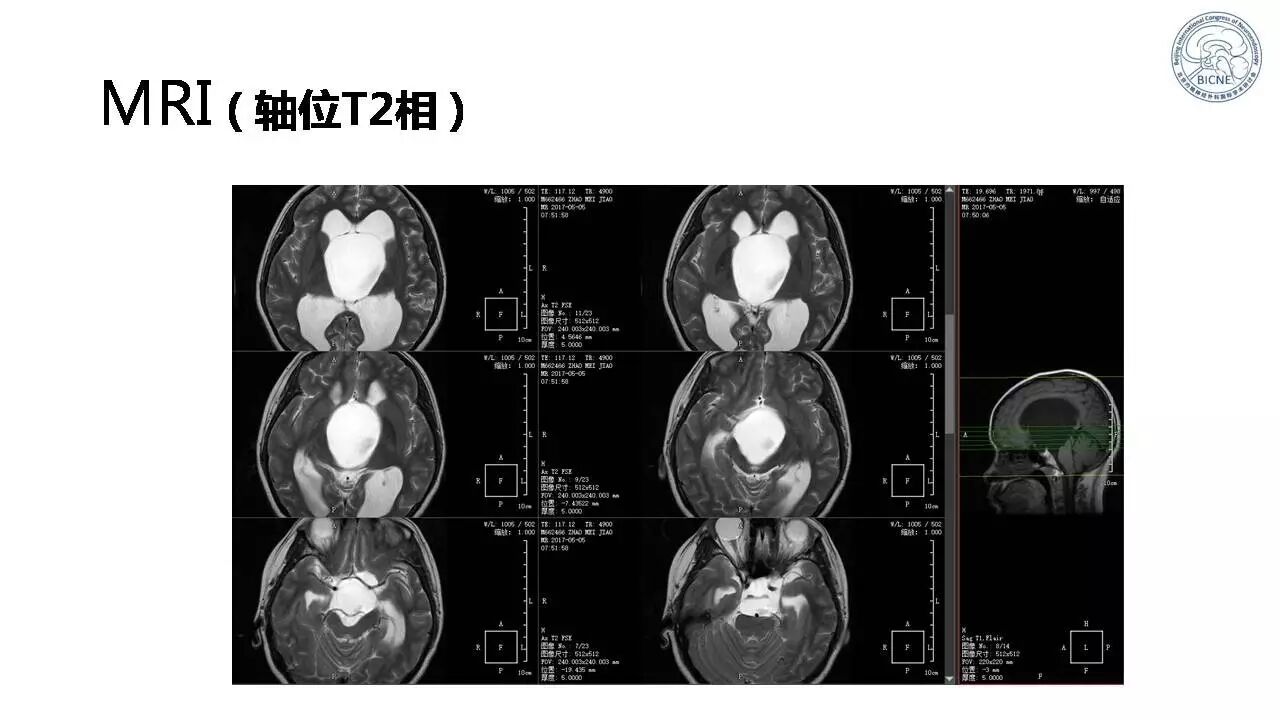

(一)张亚卓教授:脊索瘤经鼻内镜下治疗